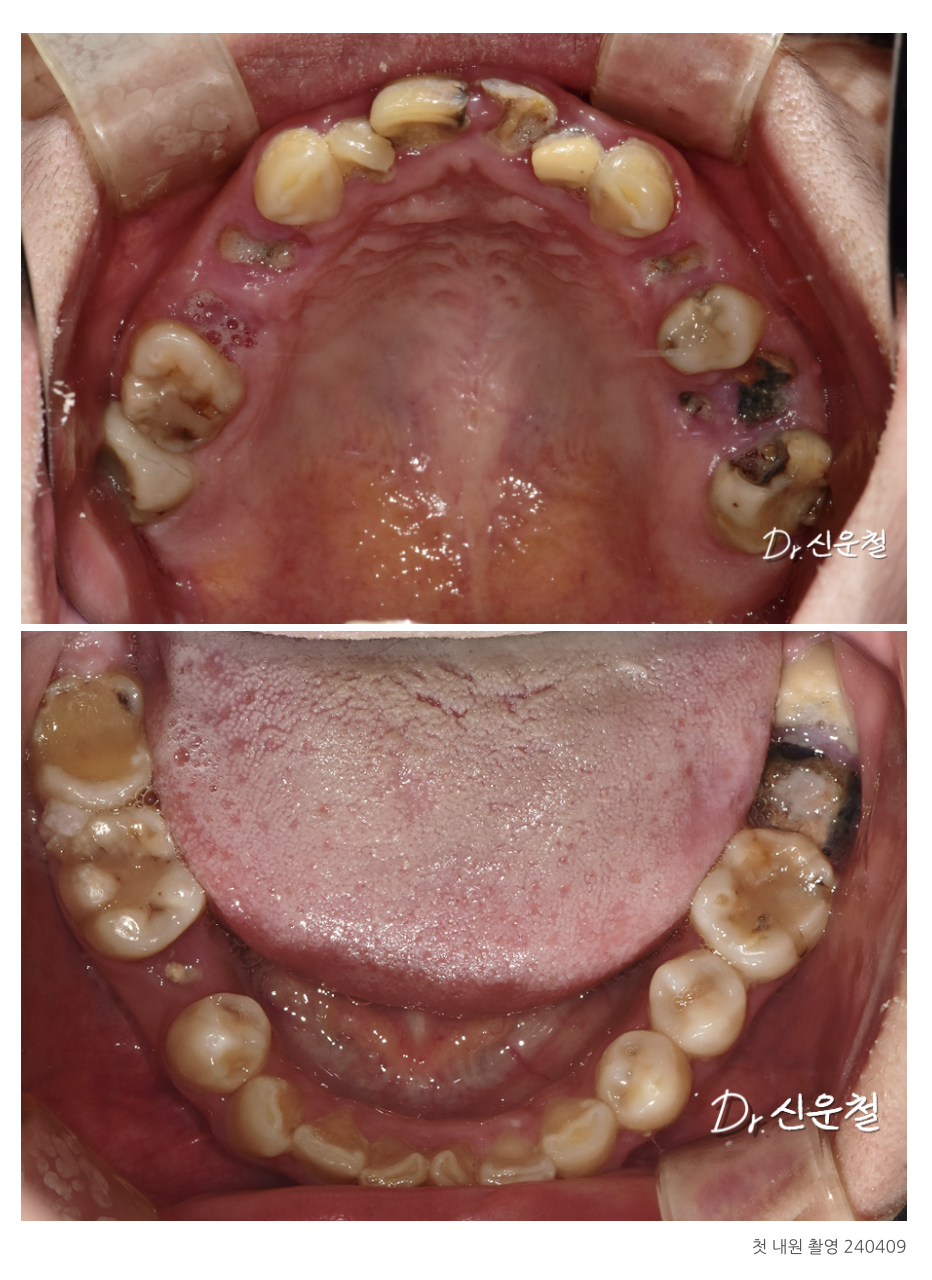

진단 결과

여러 부위의 충치와 결손치,

그리고 임플란트가 필요한 부위가 확인되었습니다.

1차 치료: 뿌리만 남은 치아 발치 (진정요법 + 무통마취 병행)

2차 치료: 남아 있는 치아는 최대한 보존

3차 치료: 임플란트 7개 단계적 식립

4차 치료: 충치 부위는 크라운, 앞니는 브릿지 보철로 자연 복원